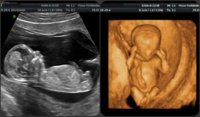

Не е исто. 4Д е ултразвучен преглед, а скрининг кој исто така се спроведува со ултразвучен апарат е детален преглед кајшто се мерат параметри кај плодот кои се витални за детектирање на одредени аномалии. Скрининг најчесто се прави еднаш на секој триместар.

Имаш прв втор и трет. Првиот и вториот скрининг ти се најважни. Првиот е за даунов синдром се прави 11-12 недела. Вториот ти е за органите на бебето се гледаат сите органи детално по ред и се прави од кај 20-23 недела.

Третиот ти е сличен како вториот пак се гледа бебето детално плодова вода папчаник.

А 4д ехо ти е сосем друго се гледа бебето во 4д целосно и поубаво.

Еве ти слика лево е обично ехо десно 4д